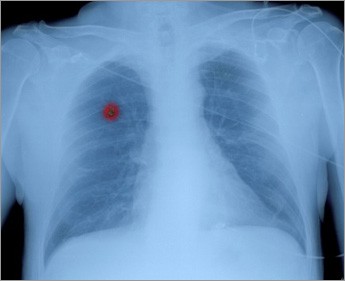

Η θεραπεία του καρκίνου του πνεύμονα μπορεί να οδηγήσει σε ίαση, μόνο εάν διαγνωστεί σε αρχικό στάδιο και χειρουργηθεί, γι΄ αυτό η μέγιστη έμφαση πρέπει να δοθεί στην πρόληψη, τόνισε ο κορυφαίος καρδιοθωρακοχειρουργός, διευθυντής του προγράμματος καρδιοχειρουργικής στο Ιδιωτικό Κέντρο “Area Health” στη Φιλαδέλφεια των ΗΠΑ και ιατρικός σύμβουλος της ηγεσίας των ΗΠΑ, Νίτσε Ζάμα.

Ο κ. Ζάμα επεσήμανε ότι οι ασθενείς υψηλού κινδύνου (καπνιστές, εργαζόμενοι σε περιβάλλον που προκαλεί επιβάρυνση στο αναπνευστικό κ.ά.), θα πρέπει να υποβάλλονται σε περιοδικό έλεγχο, που περιλαμβάνει εξέταση σε πολυτομικό αξονικό τομογράφο με πρόγραμμα χαμηλής επιβάρυνσης στην ακτινοβολία για την πρώιμη διάγνωση του καρκίνου του πνεύμονα.